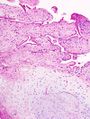

لقد تغيرت نظرتنا في العقد الماضي لتركيب ووظيفة الغضروف تغيرا مهما فأصبحنا نعتبر عملية المرض في الفصال العظمي على أنها طريقة بناء أكثر منها طريقة تنكس (Degeneration) فمن المعروف الآن أن الغضروف عبارة عن نسيج حيوي مصنوع من النوع الثاني من ألياف الكولاجين والبروتيوجليكان وخلايا غضروفية وماء وفي الحقيقة يمثل الماء نسبة تصل من 80 إلى 90 من الغضروف ومن هذا فإن عبارة إننا نمشي على الماء صحيحة لحد ما إن جزيئات البروتيوجليكان التي تميل إلى اجتذاب الماء هي في الواقع الجزيئات الكبيرة التي تملأ فراغ المطرق (Matrix) ولذلك تسمح لغضروف المفصل بتغيير شكله بطريقة انعكاسية مرتجعة (Reversible deformation) ويظهر شكلا 2 و3 غضروفا متأثرا بالفصال العظمي وغضروفا سليما .

Examples of damaged cartilage in gross pathological specimen from sows. (a) cartilage erosion (b) cartilage ulceration (c) cartilage repair (d) osteophyte (bone spur) formation.